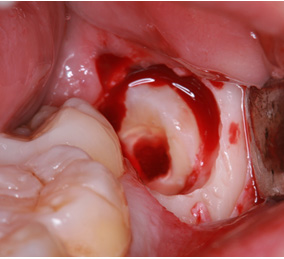

※歯肉の切開、出血を伴う写真がございます。

2回法親知らずの抜歯処置を表示する

処置の流れ

まず歯冠を切除し、疼痛がでないよう、冠部歯髄を除去してネオダイン(歯髄の鎮痛鎮静、象牙質の消毒、覆髄)を填入します。その後、粘膜骨膜弁にて完全閉鎖を行います。以下に処置の流れを示します。

処置の評価

歯冠切除量と歯根の移動量の結果です。術前の智歯(親知らず)の幅径に対して計測した智歯の長径の割合は1.21ポイント、術後は1.10ポイントで有意に差を認めました。数ヵ月待機することにより歯根は有意に近心側に移動していることを認めました。